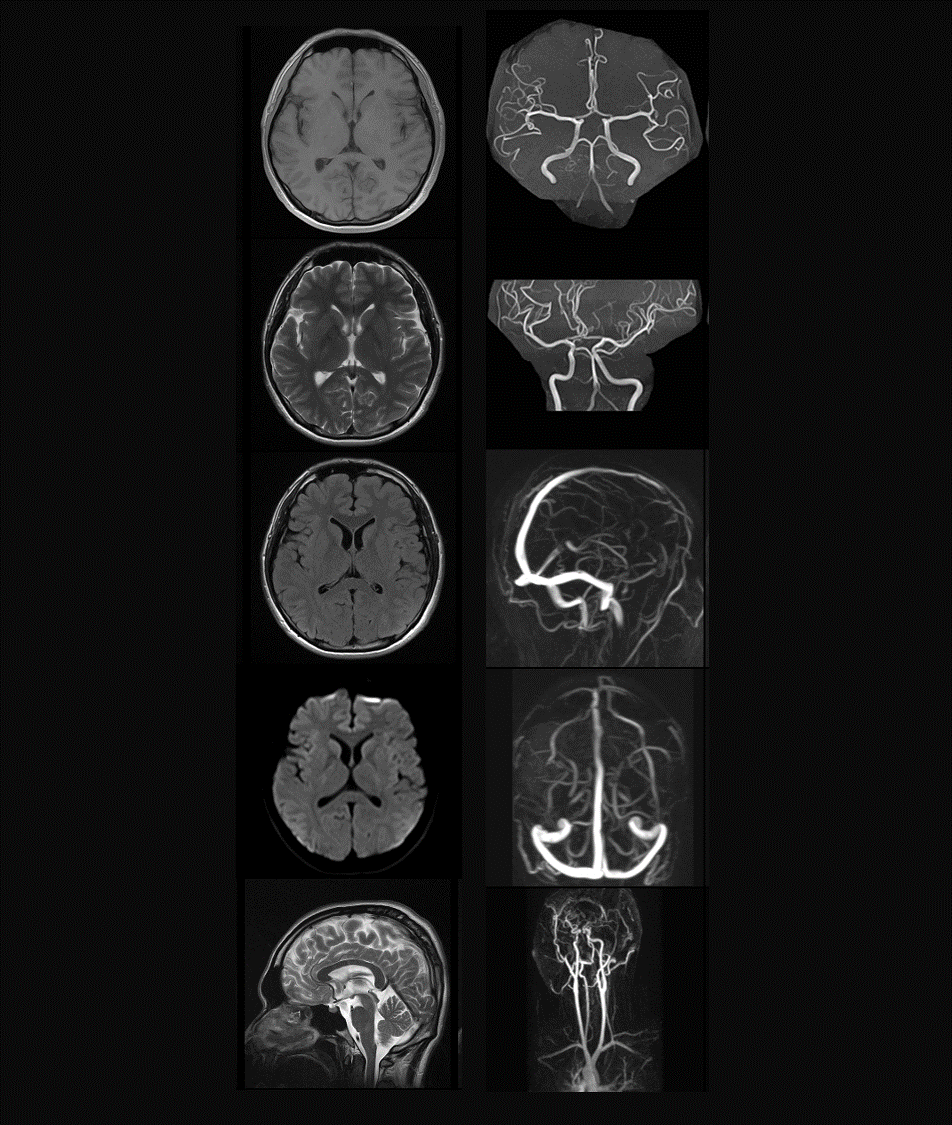

MR

中樞神經

-

醫療科技事業部